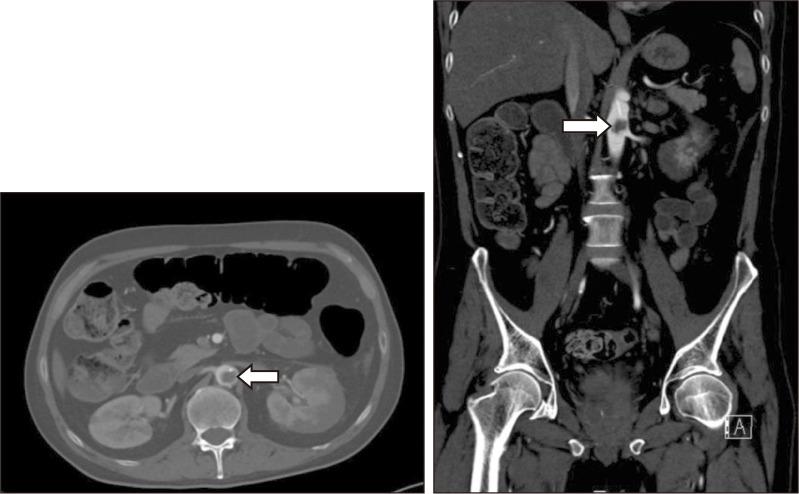

Spontaneous aortic thrombosis is exceedingly rare, and optimal treatment remains uncertain. We present an unusual case of a spontaneous aortic thrombus at the renal artery level in a patient undergoing active cisplatin treatment for urothelial carcinoma. Management included catheter-directed thrombolysis followed by thrombectomy. An open cutdown was performed on the left common femoral artery (CFA), with right groin access via a 6-Fr sheath. Clamping of the left superficial and deep femoral arteries, along with balloon occlusion of the right common iliac artery, prevented distal embolization. A Coda balloon introduced via direct left CFA puncture with a 20-Fr sheath was positioned above the aortic thrombus. After inflation, clots were trawled to the sheath, "sandwiching" the clots before removal of the balloon and sheath via the left groin. Post-operatively, the patient recovered well and received continued therapeutic anticoagulation.

自发性主动脉血栓形成极为罕见,最佳治疗方法仍不明确。我们报告了一例不寻常的病例,一名正在接受顺铂治疗尿路上皮癌的患者在肾动脉水平出现自发性主动脉血栓。治疗措施包括导管定向溶栓,随后进行血栓切除术。在左股总动脉(CFA)进行开放切开,通过一个6F鞘管进入右腹股沟。夹闭左股浅动脉和股深动脉,同时球囊封堵右髂总动脉,防止远端栓塞。通过直接经20F鞘管穿刺左CFA引入的Coda球囊置于主动脉血栓上方。球囊充气后,将血栓拖至鞘管,在通过左腹股沟移除球囊和鞘管之前对血栓进行“夹取”。术后,患者恢复良好,并继续接受抗凝治疗。